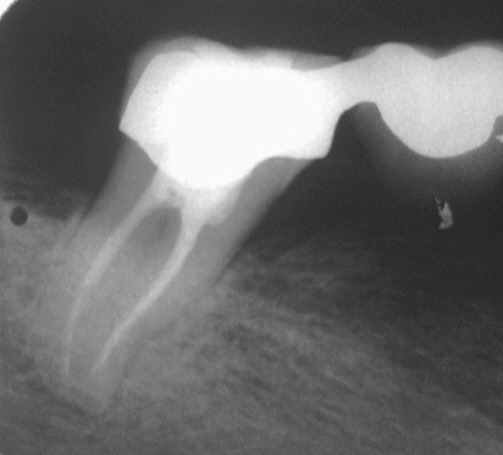

Dass man mit der Timbuktu-Methode auch Fälle lösen kann, die andere bereits aufgegeben haben, zeigt dieser Fall. Wie man im nebenstehenden OPT deutlich sieht, handelt es sich um einen ausgesprochen wichtigen, strategischen Pfeilerzahn (47). Wenn dieser verloren geht, bedeutet das für die Patientin entweder eine Neuversorgung mit einem herausnehmbaren Zahnersatz oder Implantat/en. In einem solchen Fall ist es angezeigt, die größte Geduld zu entwickeln. Angesichts der Kosten, die nicht jeder tragen kann, wird der Patient diese Geduld gerne aufbringen. Insbesondere dann, wenn Schmerzfreiheit besteht, die mit dieser Methode praktisch in jedem Falle zu erreichen ist. Diese Patientin war im Jahre 2000 von einem Spezialisten mit hohem technischen Aufwand (OP-Mikroskop, usw.) nach allen Regeln der sog. modernen Endodontie vorbehandelt worden Das OPT zeigt den deutlich beherdeten 47. Das vom Vorbehandler eingebrachte CaOH2 ist bereits entfernt. Klinisch zeigt sich ein stark klopfempfindlicher 47 mit einem Lockerungsgrad von I-II. Wenn man bedenkt, dass sich dieser Zahn in einem Brückenverbund befindet, kann man sich vorstellen, dass er -isoliert betrachtet- sicher einen Lockerungsgrad von deutlich II haben würde. Als Nebenbefund sieht man übrigens deutliche Überlastungszeichen im gesamten Gebiss, wie sie bei Pressern/Knirschern gesehen werden . Der Vorbehandler hatte den Zahn nach mehreren Versuchen mit sofortigem Verschluss nicht ruhig bekommen, schließlich ein Antibiotikum verordnet und die Patientin mit der Maßgabe weggeschickt, wenn er nun nicht ruhig werde, müsse man ihn eben extrahieren.

Links sehen wir den Zahn nach unserer ersten WF nach ca. 8-wöchiger Behandlung nach unserer Methode. Beschwerdefreiheit und Lockerungsgrad L=0 waren nach Ruhigstellung und Schienen-Eingliederung rasch erreicht worden. Die Aufhellung ist deutlich reduziert, aber noch nicht verschwunden. Nichts ist überpresst. Wie man sieht, ist es auch uns nicht gelungen, den Zahn augrund seiner schwierigen Anatomie bis zum Apex aufzubereiten, geschweige denn, darüber hinaus, wie wir es in einem solchen Fall gerne hätten.